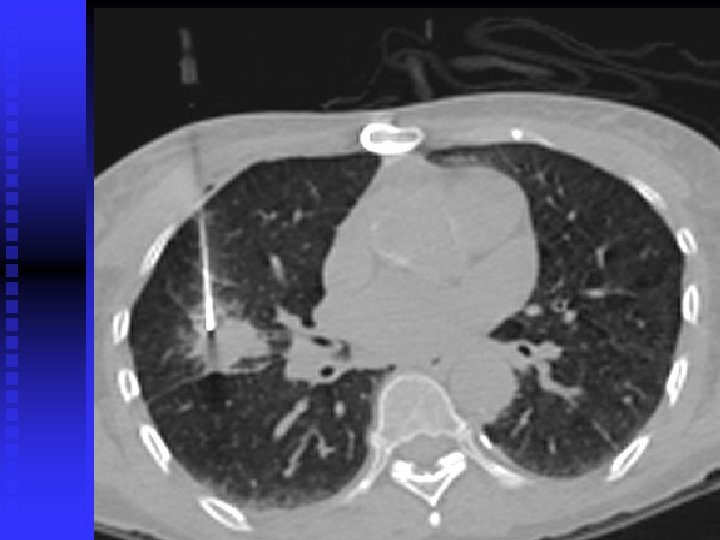

Case 3 56 year old woman, ex smoker, large goitre n Found to have a Nodule (Solitary pulmonary nodule) on CT scan = incidental n Interval scan if nodule < 1 cm or looks benign for up to 2 years n PET scan +/ CT guided biopsy if > 1 cm n If suspicious, then can consider wedge resection or lobectomy n